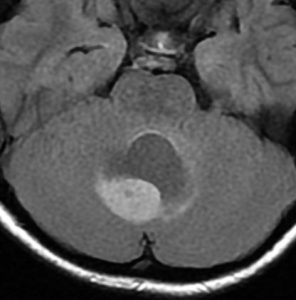

手術翌日のMRIです。小脳失調症状の出現はなく,抜糸してすぐに退院して普通の生活に戻れました。

この画像を見れば,後頭下開頭テント下法 infratentorial approach では,小脳切断しなければ腫瘍に届かないことが理解できると思います。